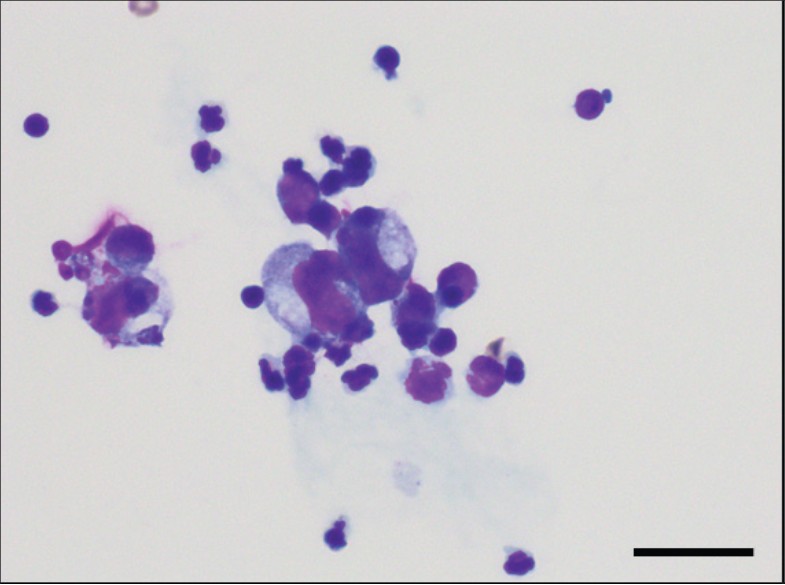

初次就诊后的第12天,进行了非镇静CT。未使用麻醉,将患者固定在亚克力笼中(CT胶囊)。CT显示胰腺呈肿瘤样增大,腹膜背侧不规则散在结节聚集,右肺下叶呈磨玻璃样改变(下图)。由于未进行血管造影,无法评估血管特征和软组织肿块的更详细鉴别。

↑ CT扫描。显示了(A)上腹部和(B)胸部的横断面CT图像。肠系膜脂肪显示出以增大且呈肿瘤样胰腺(*)为中心的散在结节,且结节轮廓不规则(箭头)。右肺下叶观察到磨玻璃样改变(三角)。